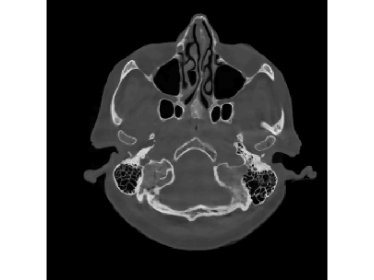

Finally, we apply the proposed method on a clinical head dataset. The data are acquired with a Siemens Artis zee angiographic C-arm system (Siemens Healthcare GmbH, Forchheim, Germany). In this experiment, we choose one slice of a 3D clinical head dataset as the ground truth image (Fig.9) and reproject it to simulate the acquired sinogram data in the fan-beam system with the following trajectory parameters: the source-to-isocenter distance is 750 mm and isocenter-to-detector distance is 450 mm. The angular step is 1 degree and the total scan range is 360 degrees. The equal-spaced detector length is 620 mm with the pixel length 111 mm.

The full projections are shown in Fig.10. When the detection range κ𝜅\kappa is limited, there could be saturation for the projection. In Fig.10 and Fig.10, observations for κ=0.6pmax𝜅0.6subscript𝑝\kappa=0.6p_{\max} and κ=0.4pmax𝜅0.4subscript𝑝\kappa=0.4p_{\max} are displayed, respectively. Our task is to recover the image from the saturated projections via M1bit-CS-ISD. The results are compared with FBP and SART, two standard CT reconduction frameworks. For FBP, we apply the modification given by [38] that utilizes water cylinder extrapolation to remedy missing projections caused by truncation or overexposure. For SART, one can remove those saturated projections when they are found, for which the ISD can be used as well. We denote this method as SART-ISD, of which the detection scheme is as the same as M1bit-CSR-ISD but SART is used as the reconstruction method.

Figure 9: Reconstruction results for the clinical data (κ=0.6pmax𝜅0.6subscript𝑝\kappa=0.6p_{\max}): (a) ground truth; (b) FBP-WCE; (c) SART-ISD; (d) M1bit-CSR-ISD.

For κ=0.6pmax𝜅0.6subscript𝑝\kappa=0.6p_{\max}, the reconstruction results of FBP-WCE and SART-ISD are given in Fig.9 and 9, respectively. As shown before, the traditional FBP method cannot handle the saturated data. With water cylinder extrapolation, the reconstruction quality has been improved but loss of clear patient boundaries still happens. The overall performance of SART-ISD is slightly better than FBP-WCE but capping artifact can be identified at the object border. Further improvement is obtained using the proposed M1Bit-CSR-ISD to acquire information from the saturated data. As shown in Fig.9, most of outer boundaries are nicely restored and streaking artifacts are effectively eliminated.